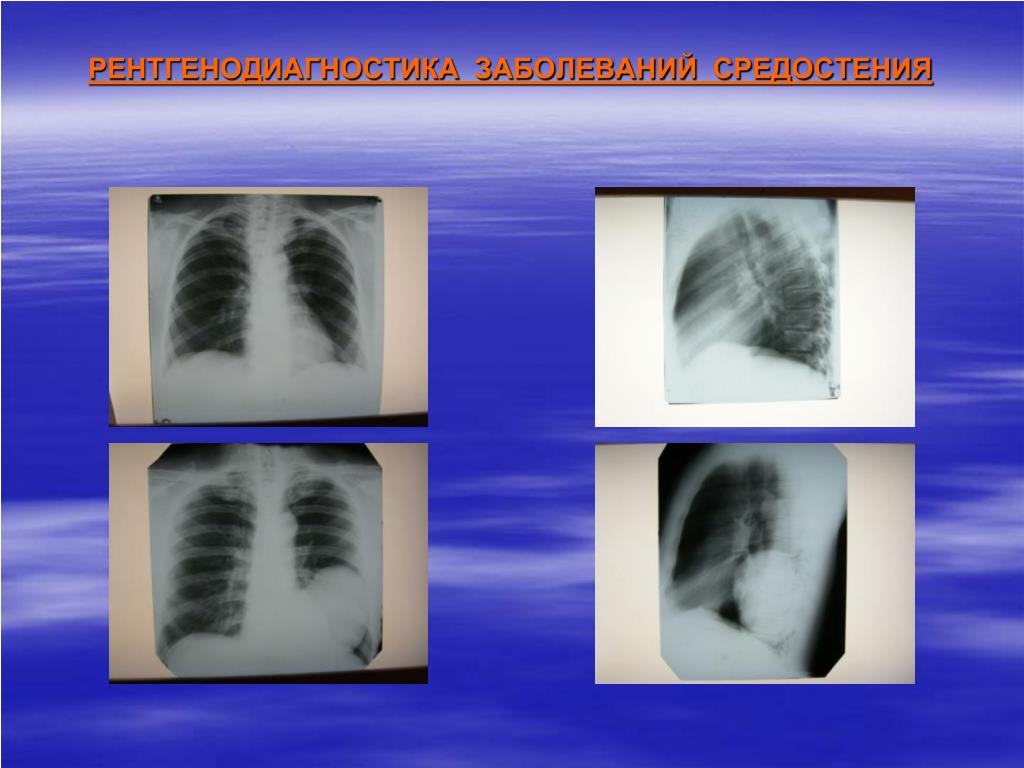

Рентгеновские снимки тератомы средостения: Диагностика и лечение

Раздел: Фотоэссе